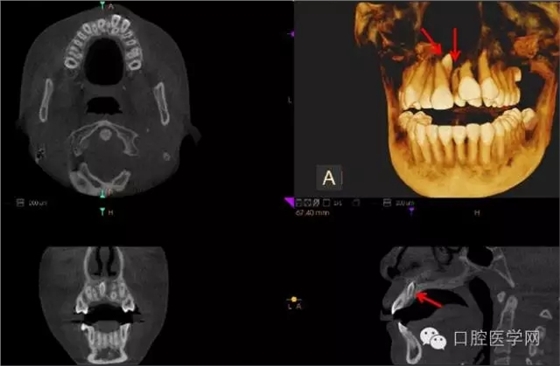

額外牙

X線表現(xiàn):最多見于上頜兩中切牙之間;圓錐形,根短小;拍攝X線片可確定額外牙的數(shù)目、位置、形態(tài)與鄰牙的關(guān)系。